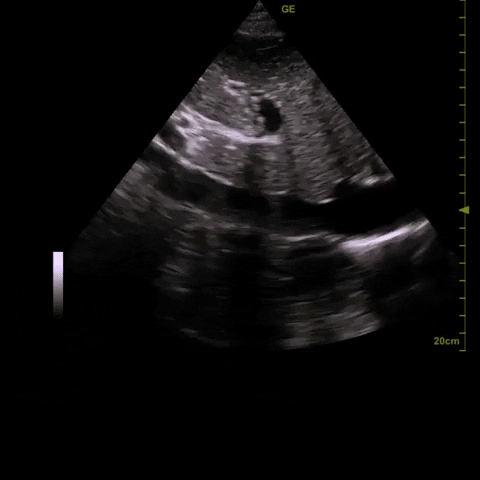

1) pleural effusion (suggestion of this on CXR) – they were hoping for a diagnostically drainable pocket of fluid

Here are clips from the initial lung POCUS: